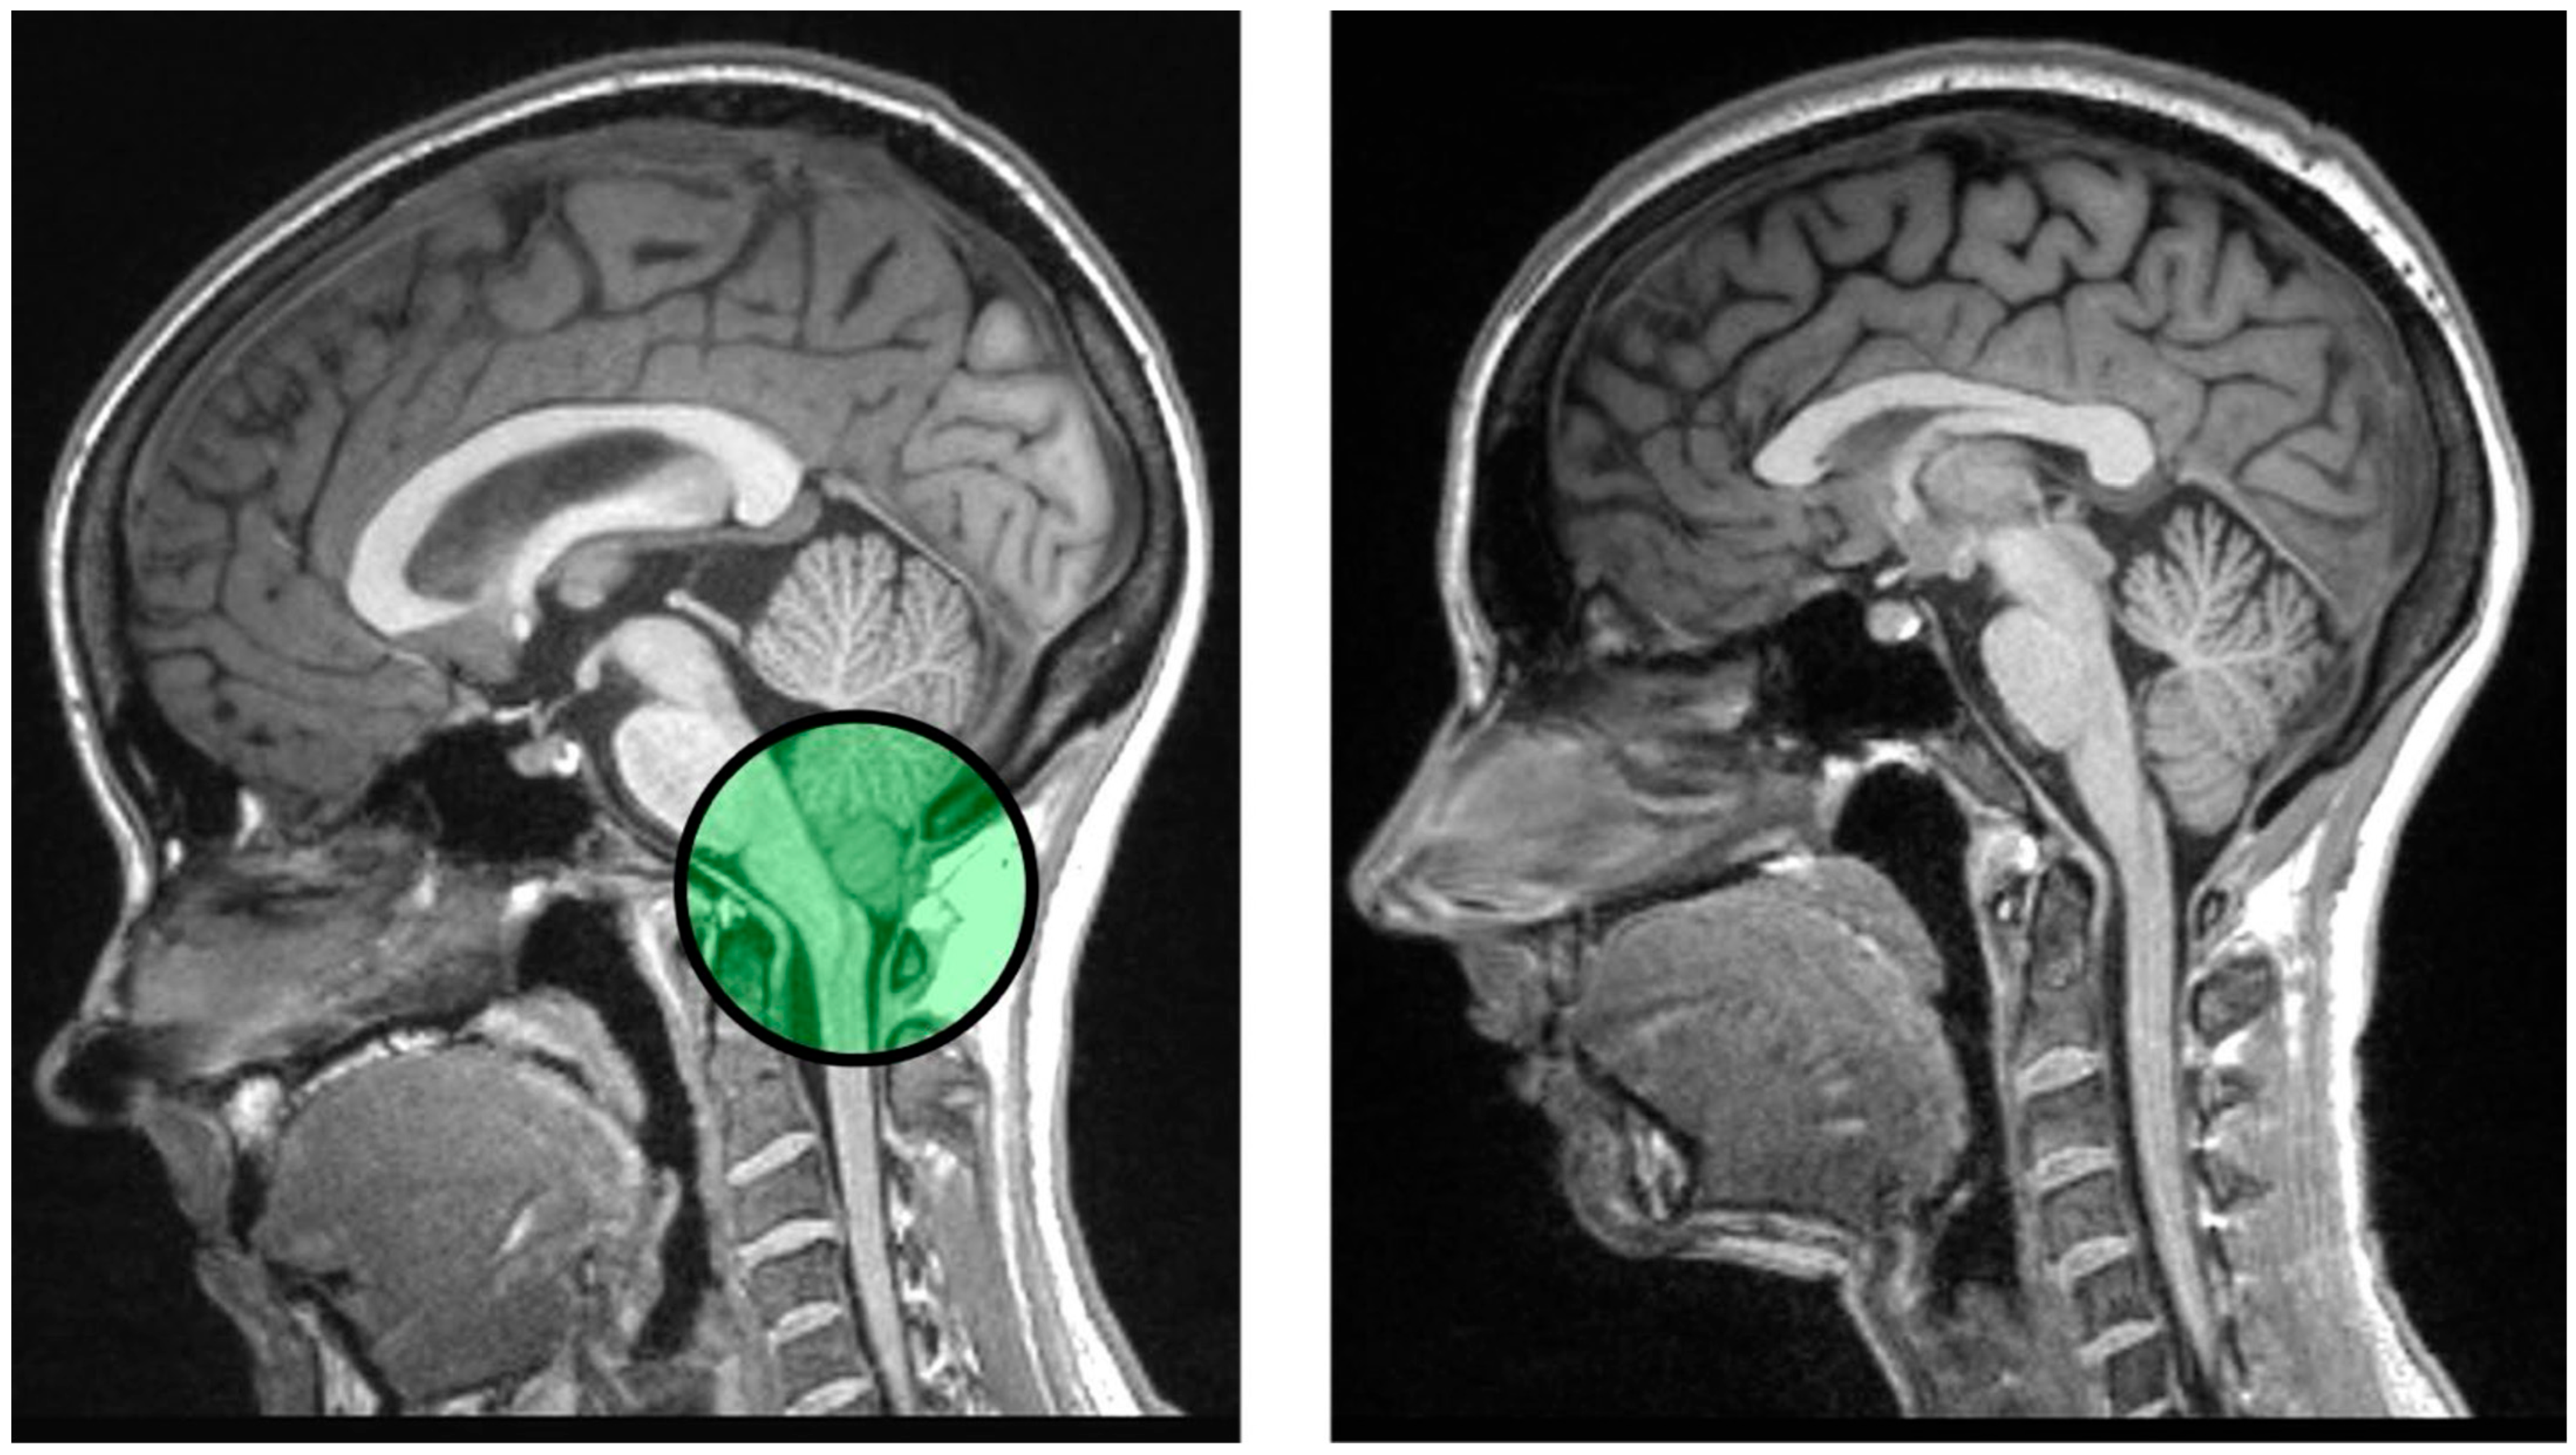

7. Chronic Pain as a Modulator of Episodic Memory and the Link to Chiari Malformation

8. Theoretical Application: Pathogenesis of Central Pain Sensitization in Chiari Malformation Type I